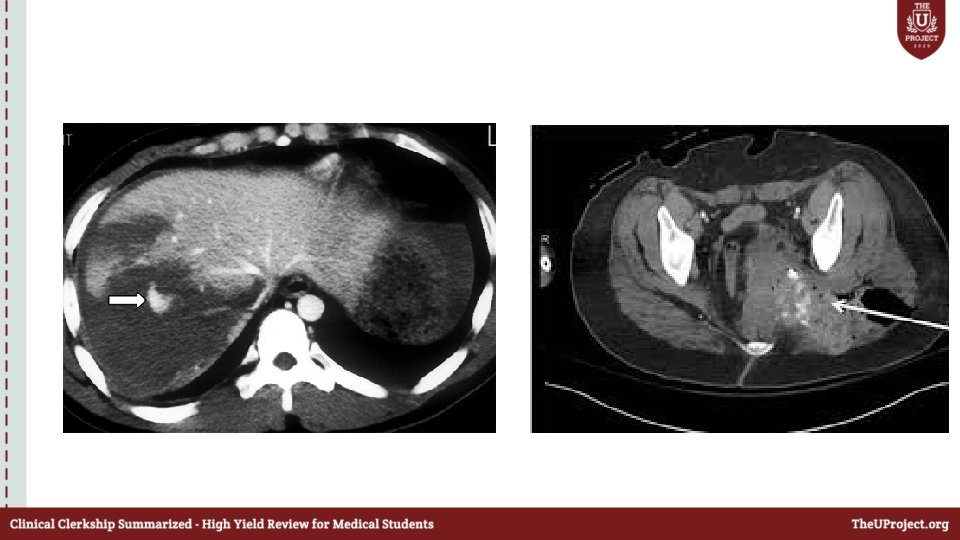

Case 5 • 30 year old man ; fell from a hight of 3 meters while he was cleaning the roof of his house ; brought by EMS with C collar and backboard in place. • What will you do next ?

Primary survey • A: Patent , C-collar is in place • B: SPO 2 84% ; RR 20 • C: BP 110/80 ; HR 100 • D: GCS : 14 ; pupils are reactive • E: multiple abrassions in the abdomen

What do you want to do next ?

Secondary survey • Normal • What do want to do next ?

Free fluid with no solid organ injury What injuries will u expect & what should you do next ?